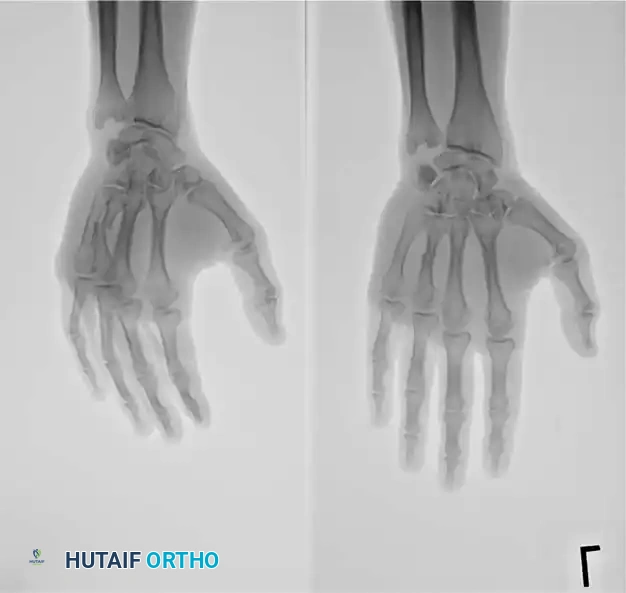

Fig. 64-31 Dislocation of fourth and fi fth carpometacarpal joints. A, Clinical appearance of hand before reduction. Note dorsoulnar hand swelling consistent with injury. B, Posteroanterior view. C, Lateral view. D, Oblique view. E and F, Traction was adequate to reduce, and splint was satisfactory to maintain reductions.

Standard posteroanterior (PA) radiographs may appear deceptively benign. The hallmark of a CMC dislocation on a PA view is the loss of the parallel joint surfaces (the "M" line) at the carpometacarpal articulations.

A true lateral radiograph is an absolute necessity for accurate diagnosis, as it will clearly demonstrate the dorsal or volar displacement of the metacarpal bases relative to the carpal row.

Oblique views further delineate the extent of articular comminution and subluxation.